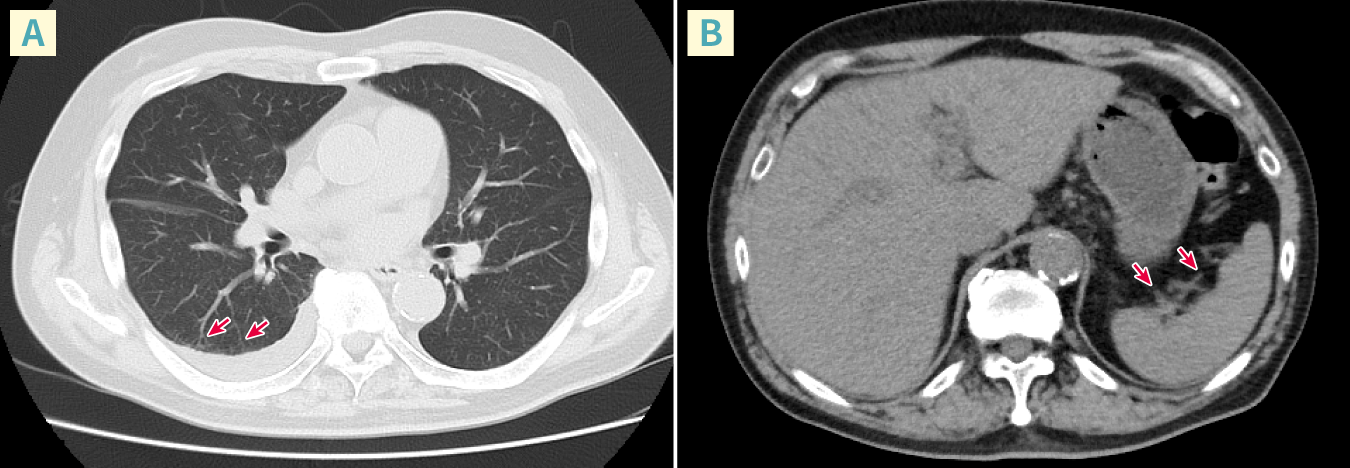

図2 症例の胸部CT画像(A)と腹部CT画像(B)